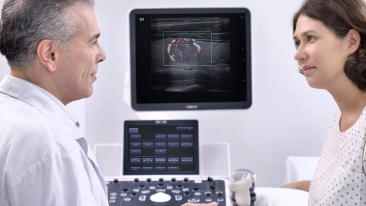

Como un socio personal, el DC-70 Exp con X-Insight? ?se centra en lo que verdaderamente importa, ayudando al usuario a administrar su prĂĄctica clĂnica con facilidad y seguridad.

BasĂĄndose en una profunda comprensiĂłn de las necesidades del usuario, el DC-70 con X-Insight estĂĄ dise?ado para ofrecer una alta eficiencia con imĂĄgenes de precisiĂłn, la cual se ve potenciada por una eXpress Clarity, eXceptional Intelligence, eXceeding Experience.